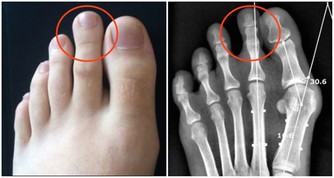

4. 晚餐與尿路結石

人體的排鈣高峰期一般在晚餐後4、5個小時,

如果晚飯吃得太晚,在排鈣高峰期已進入睡眠。

不能通過尿液及時排出體外,使尿中鈣不斷增加,形成結晶,長期積累形成結石。